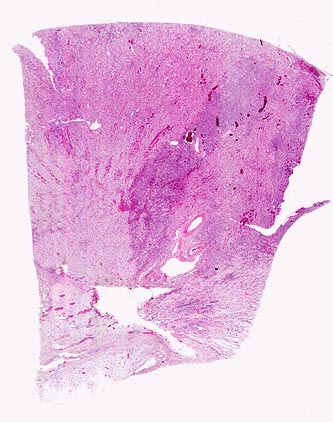

Vorkommen: